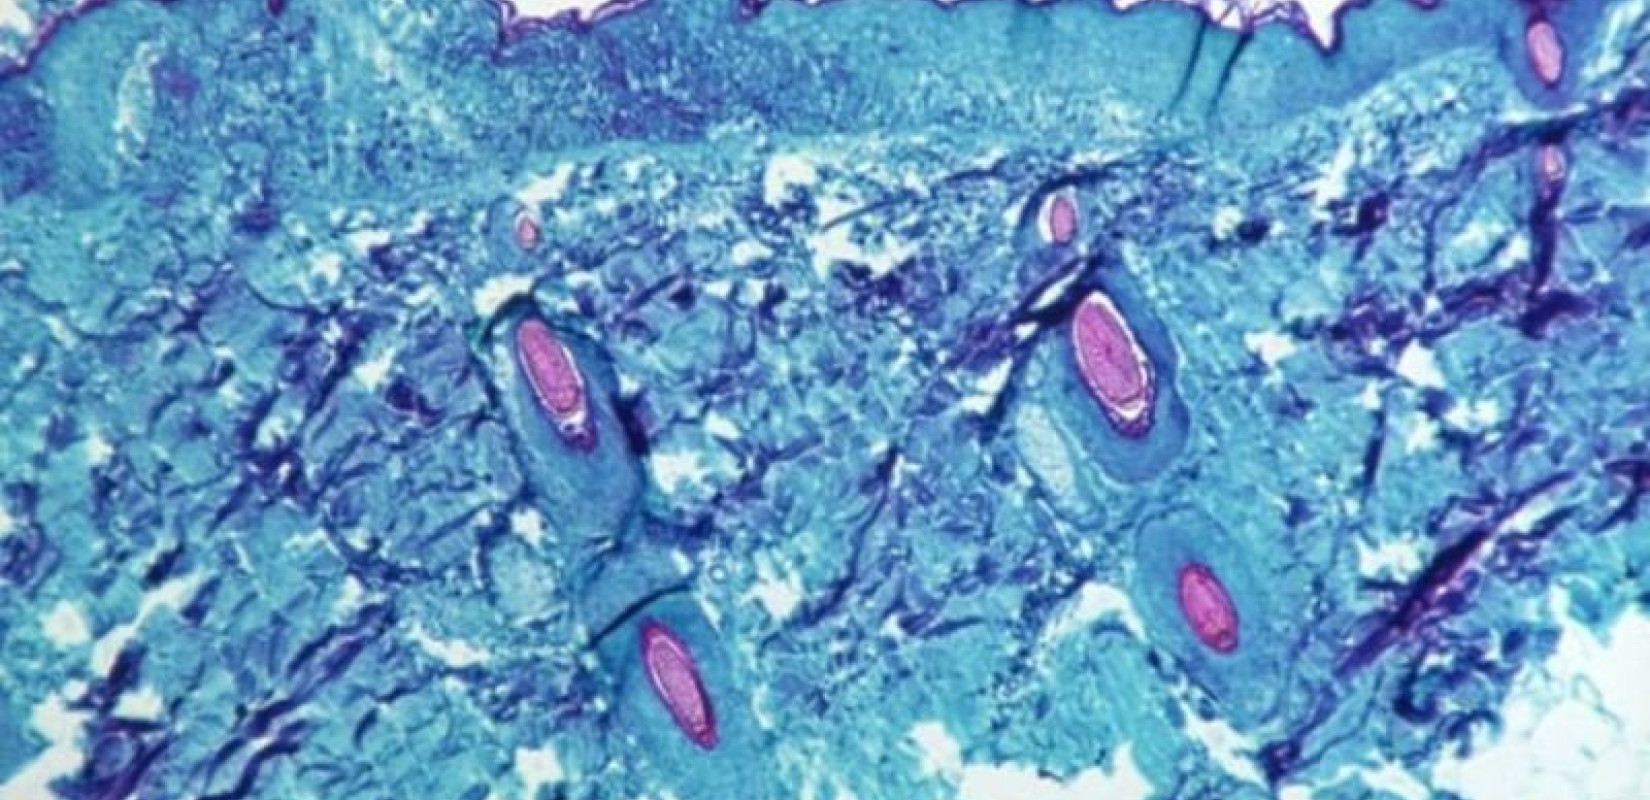

Σε συναγερμό τέθηκαν από χθες οι υγειονομικές Αρχές της Θεσσαλονίκης για ύποπτο κρούσμα της ευλογιάς των πιθήκων σε 61χρονο άνδρα από το Μαρόκο, ο οποίος νοσηλεύεται στο νοσοκομείο Παπαγεωργίου.

Ο 61χρονος βρίσκεται ήδη σε απομόνωση σε θάλαμο αρνητικής πίεσης, ενώ σήμερα Παρασκευή -πιθανότατα το μεσημέρι- αναμένονται τα αποτελέσματα των εξετάσεων από τα δείγματα που έχουν σταλεί στο ΑΠΘ, για να φανεί αν έχει όντως μολυνθεί από την θανατηφόρα νόσο που έχει σκορπίσει ανησυχία στην Ευρώπη το τελευταίο διάστημα. Επιπλέον, όπως προβλέπεται, ενημερώθηκε σχετικά και ο ΕΟΔΥ.

Σύμφωνα, πάντως, με πληροφορίες, ο άνδρας είναι σε πολύ καλή κατάσταση ενώ έχει πολύ περιορισμένα συμπτώματα.

Στο μεταξύ, όπως προειδοποίησε εχθές ο Περιφερειακός Διευθυντής Ευρώπης του Παγκόσμιου Οργανισμού Υγείας, Χανς Κλούγκε, «η Ευρώπη παραμένει στο επίκεντρο της μεγαλύτερης και γεωγραφικά πιο εκτεταμένης επιδημίας της ευλογιάς των πιθήκων που έχει αναφερθεί ποτέ εκτός των ενδημικών περιοχών της δυτικής και κεντρικής Αφρικής», τονίζοντας πως ο κίνδυνος εξάπλωσης μέσα στο καλοκαίρι παραμένει υψηλός.

Όπως τόνισε η καμπύλη κρουσμάτων ήταν απότομη τις τελευταίες 2 εβδομάδες, ενώ περιέγραψε όσα γνωρίζουν οι ειδικοί για την ευλογιά των πιθήκων μέχρι αυτή τη στιγμή. «Ακόμη κι αν καθημερινά παρουσιάζονται νέοι ασθενείς, οι έρευνες σε προηγούμενα περιστατικά δείχνουν ότι η επιδημία στην περιοχή μας (σ.σ. Ευρώπη) ήταν σίγουρα σε εξέλιξη ήδη από τα μέσα Απριλίου» ανέφερε.

Σημειώνεται πως, προ ημερών, η καθηγήτρια Επιδημιολογίας στην Ιατρική Σχολή του ΕΚΠΑ, Αθηνά Λινού, επεσήμανε πως θεωρεί «απίθανο να μην εμφανιστεί κρούσμα και στην Ελλάδα». Γι’ αυτό δίνει έμφαση στους τρόπους μετάδοσης, τα συμπτώματα και τα μέτρα προστασίας, τονίζοντας ότι η ιχνηλάτηση των επαφών, ο γρήγορος εντοπισμός νέων κρουσμάτων και η απομόνωση, είναι οι παράγοντας που θα σπάσουν την αλυσίδα μετάδοσης.

«Είναι απίθανο να μην έχουμε κανένα κρούσμα στην Ελλάδα, εκτός και αν μπορέσουμε τις επόμενες ημέρες να εξαλείψουμε τη νόσο, αλλά πλέον είναι σε 19 χώρες. Πώς θα μπορέσουν αυτές οι χώρες να βρουν τις επαφές των 200 κρουσμάτων που έχουν;», αναρωτήθηκε.

Αναφορικά με τη μεταδοτικότητα, τόνισε ότι ακόμα δε «γνωρίζουμε τη μεταδοτικότατα αυτής της μορφής που κυκλοφορεί σήμερα στην Ευρώπη. Βλέπουμε ότι κάθε 2 με 3 μέρες διπλασιάζονται τα κρούσματα οπότε πρέπει να πάρουμε άμεσα μέτρα».

Σύμφωνα με την ίδια «υπάρχουν περισσότερα κρούσματα», καθώς «η ευλογιά των πιθήκων, όπως και η ανθρώπινη ευλογιά, κάνει περίπου δύο εβδομάδες για να έχει ορατά συμπτώματα. Άρα όποιοι έχουν κολλήσει σήμερα θα δούμε τα περιστατικά αυτά τις επόμενες δύο εβδομάδες».